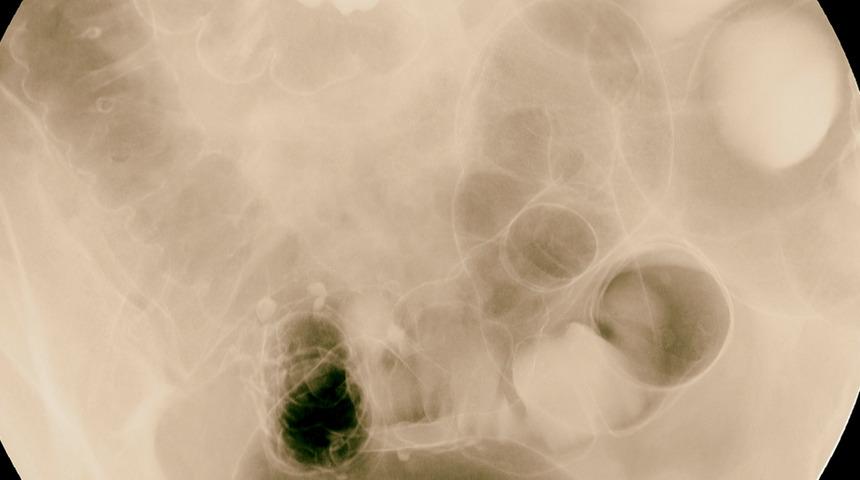

Yaklaşık iki yıldır dünyada olduğu gibi ülkemizde de tüm hızıyla devam eden Covid-19 pandemisi sürecinde, Crohn ve Kolit hastaları ‘bağışıklığı baskılayacağı’ düşüncesiyle ilaçlarını kesebiliyorlar. Ancak dikkat! Acıbadem International Hastanesi Gastroenteroloji Uzmanı Dr. Öğretim Üyesi Özdal Ersoy, Covid-19’a yakalanma kaygısıyla doktora danışılmadan ilaçların kesilmesinin bu hastalıkların uyanmasına yol açabileceğini vurgulayarak “Bazı ilaçlarda dozların azaltılması gerekse de bu ayarlamayı mutlaka doktorun yapması gerekiyor. Aksi halde doktora danışılmadan ilaç kullanmayı bırakmak ya da dozlarını azaltmak çok ciddi tehlikelere yol açabilir” diyor. Genel olarak inflamatuar bağırsak hastalıkları olarak adlandırılan bu iki hastalığın, sindirim sistemi dışında da belirti verebildiğini belirten Dr. Öğretim Üyesi Özdal Ersoy, 1-7 Aralık Crohn ve Kolit Farkındalık Haftası kapsamında yaptığı açıklamada, inflamatuar bağırsak hastalıklarında en sık görülen 8 belirtiyi anlattı, önemli uyarılar ve önerilerde bulundu.

Karında huzursuzluk veren ya da kramplar şeklinde gelen şiddetli ağrılardır. Tuvalete gitmekle ağrının şiddeti değişmez. Ağrıya ishal eşlik edebilir. Yemek yemekle ağrı şiddetlenebilir. Sebebi açıklanmamış uzun süreli karın ağrılarında Crohn hastalığı mutlaka akla getirilmelidir.

İshal genellikle 3 haftadan uzun sürer. Çoğunlukla kanlı ve mukuslu yani beyaz sümüksü akıntı şeklindedir. Gece uykudan uyandırabilir. Crohn hastalığında bol ve sulu ishal olabilir. Ülseratif Kolit hastalığında ise ishal yumuşamış dışkı şeklinde ve muhakkak kanlı görülür.

Crohn hastalığı bağırsağın tüm katmanlarını tuttuğu için, özellikle makat bölgesinde bağırsaktan cilde açılan tüneller (fistüller) ya da cilde açılamamış apselere yol açar. Apseler şiddetli makat ağrısı yapar. Apse fistülleştiğinde ise ağrı azalır ancak makat çevresinde akıntı, kirlenme başlar. Fistül vajen içine olduysa, vajenden dışkı, kan ya da gaz gelebilir.